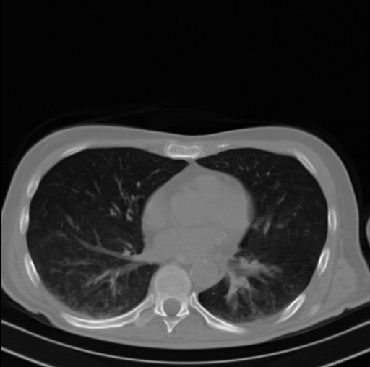

Early and reliable COVID-19 diagnosis based on chest 3-D CT scans can assist medical specialists in vital circumstances. Deep learning methodologies constitute a main approach for chest CT scan analysis and disease prediction. However, large annotated databases are necessary for developing deep learning models that are able to provide COVID-19 diagnosis across various medical environments in different countries. Due to privacy issues, publicly available COVID-19 CT datasets are highly difficult to obtain, which hinders the research and development of AI-enabled diagnosis methods of COVID-19 based on CT scans. In this paper we present the COV19-CT-DB database which is annotated for COVID-19, consisting of about 5,000 3-D CT scans, We have split the database in training, validation and test datasets. The former two datasets can be used for training and validation of machine learning models, while the latter will be used for evaluation of the developed models. We also present a deep learning approach, based on a CNN-RNN network and report its performance on the COVID19-CT-DB database.